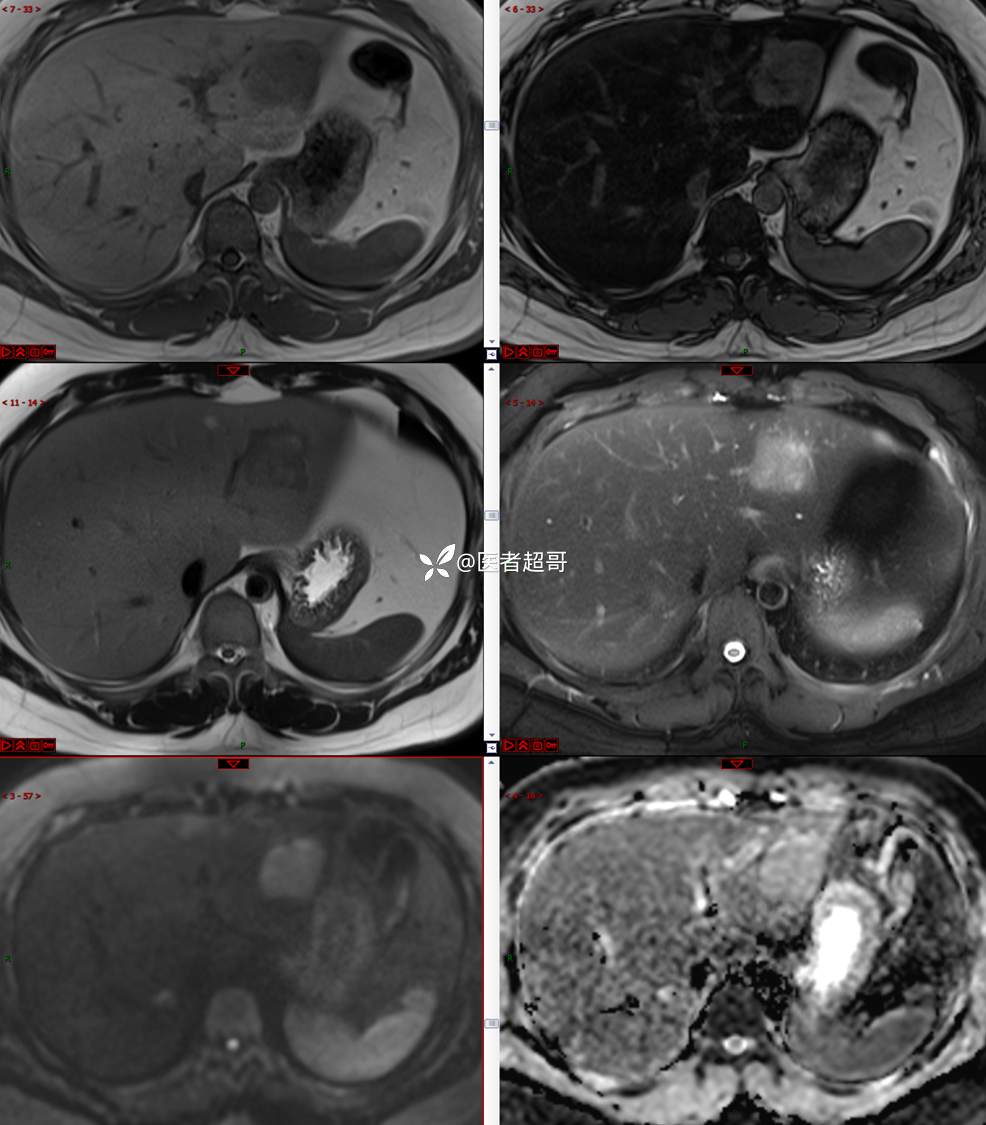

【影诊笔记685】男,31y,发现肝占位性病变5天就诊,请诊断分析,有病理结果!

主 诉:发现肝占位性病变5天。

现病史:患者缘于5天前体检时发现肝占位性病变,未予以特殊处置。现患者为求系统诊治就诊于我院,行普美显提示:肝左叶富血供占位,请结合临床及其他检查,肝多发血管瘤,脂肪肝,肝囊肿,请结合临床。门诊以“肝占位性病变”收入我科。病程中,饮食睡眠可,二便可,近期体重未见明显变化。